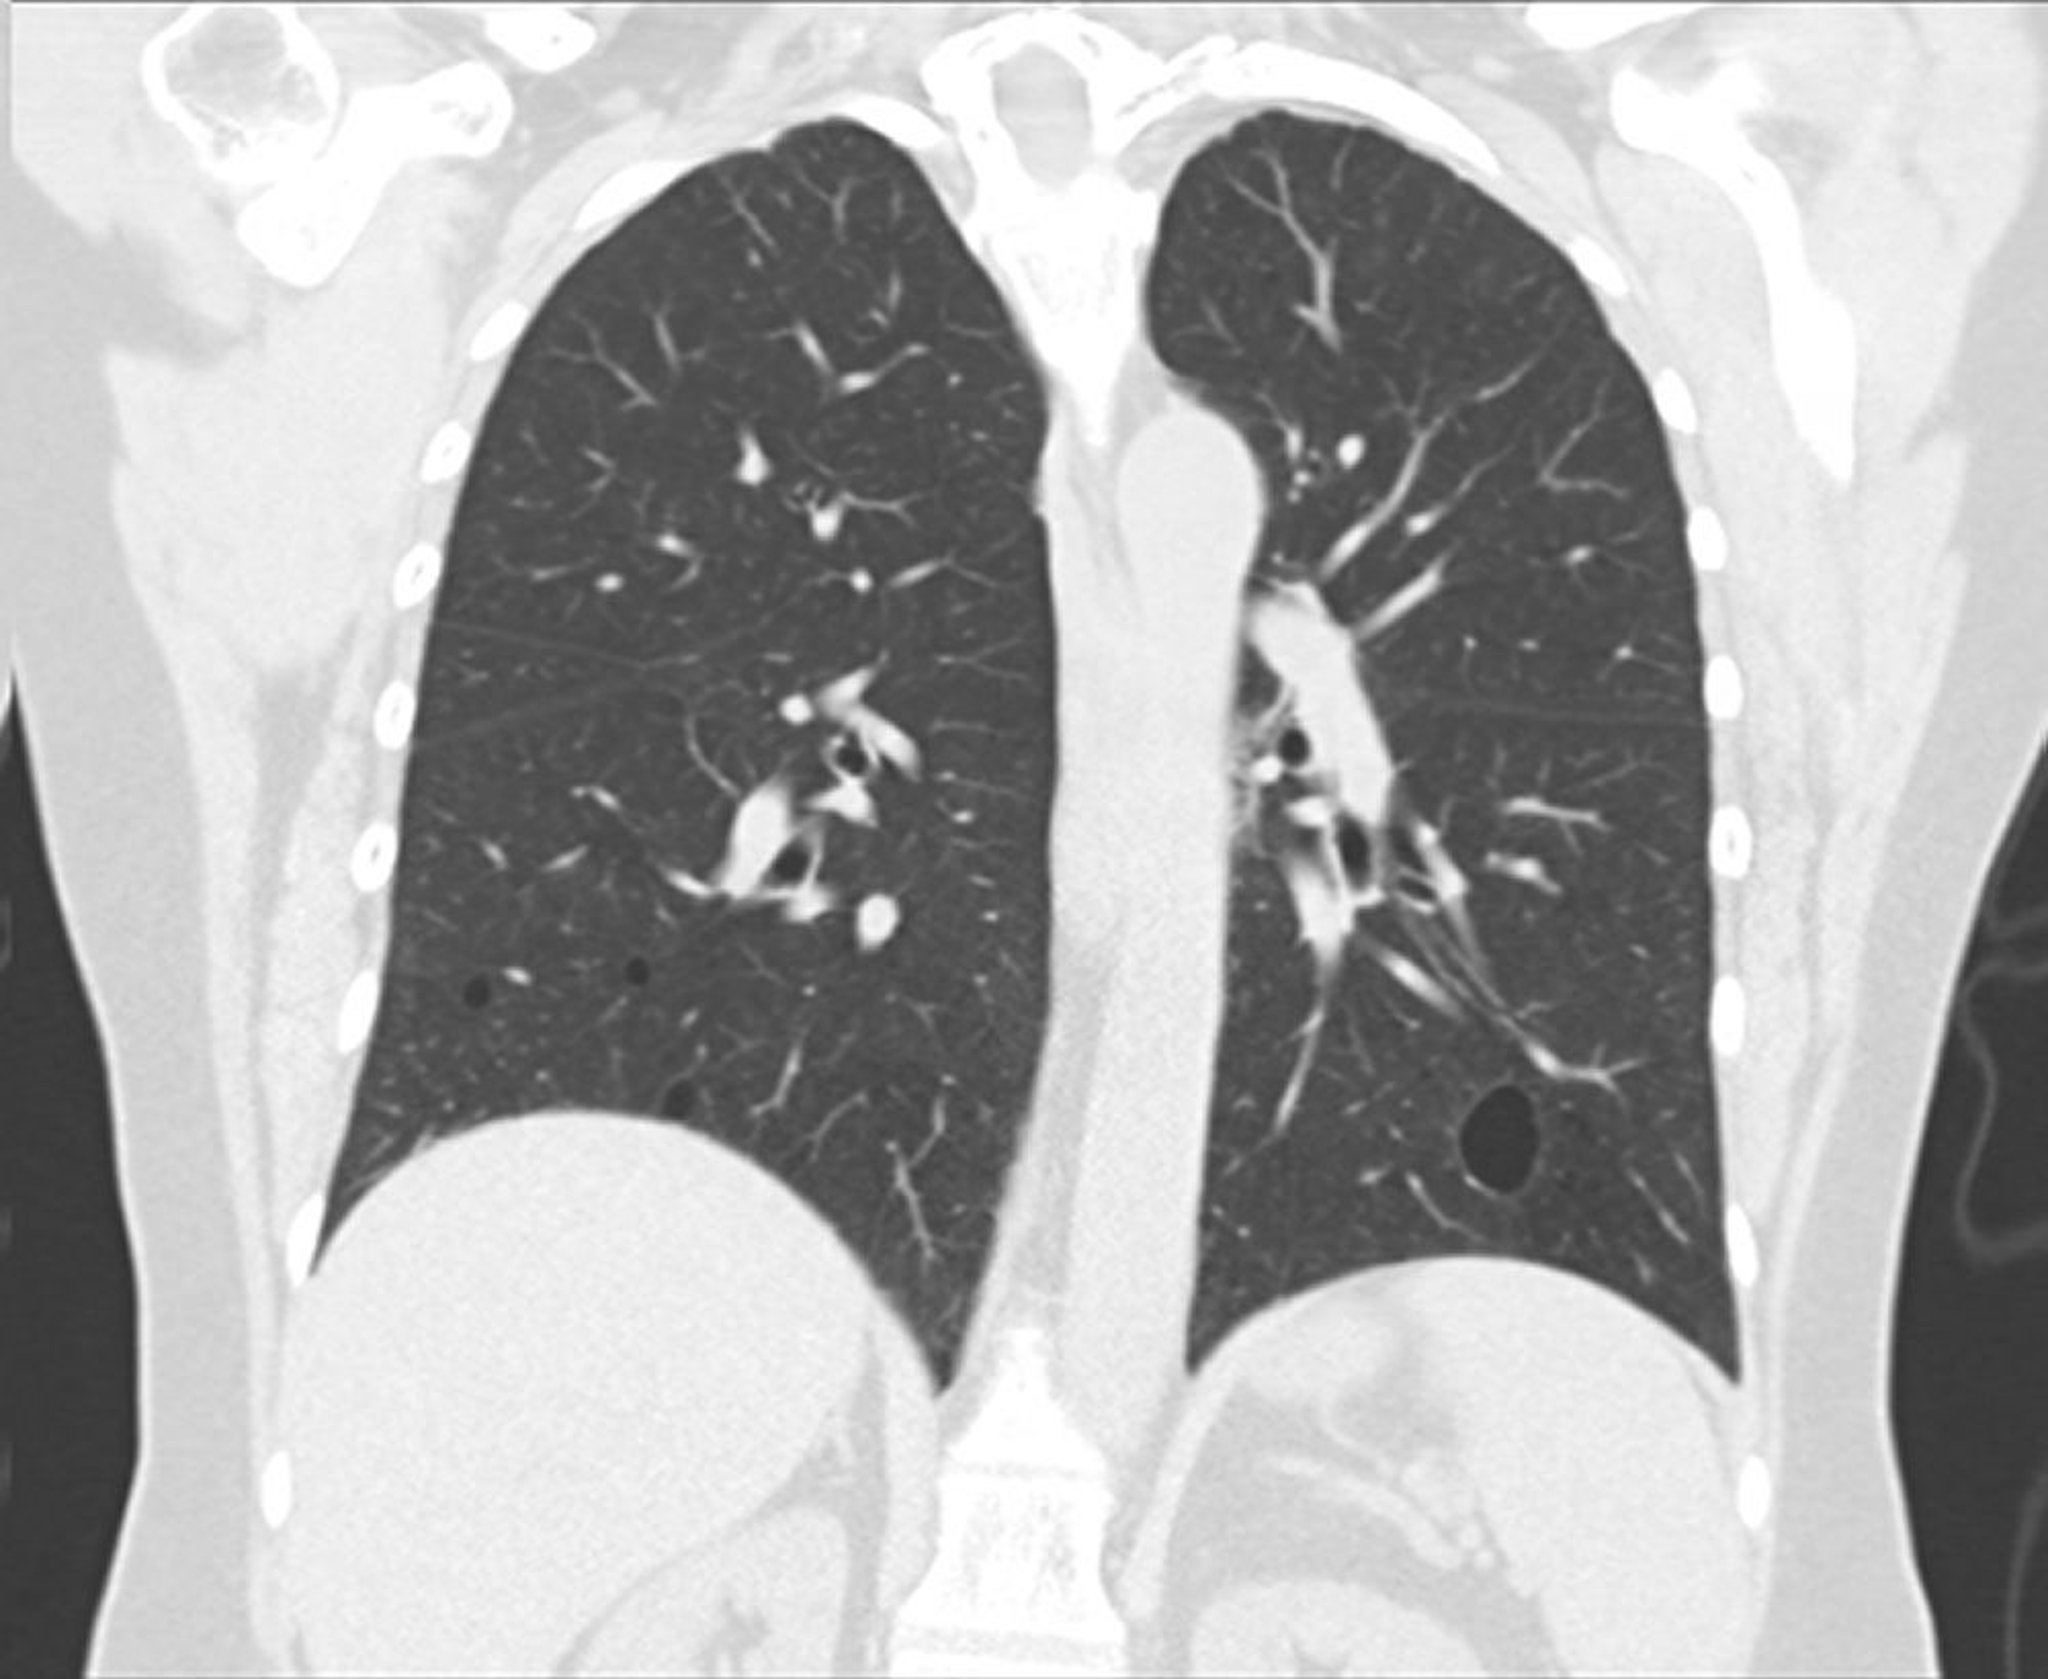

Lymphozytische Interstitielle Pneumonie

Dieses Bild zeigt eine lymphozytische interstitielle Pneumonie als Folge des Sjögren-Syndroms. Auf diesem koronalen CT-Schnitt sind gut umschriebene Zysten in den beidseitigen Unterlappen zu sehen.

This image courtesy of Tami Bang, MD.